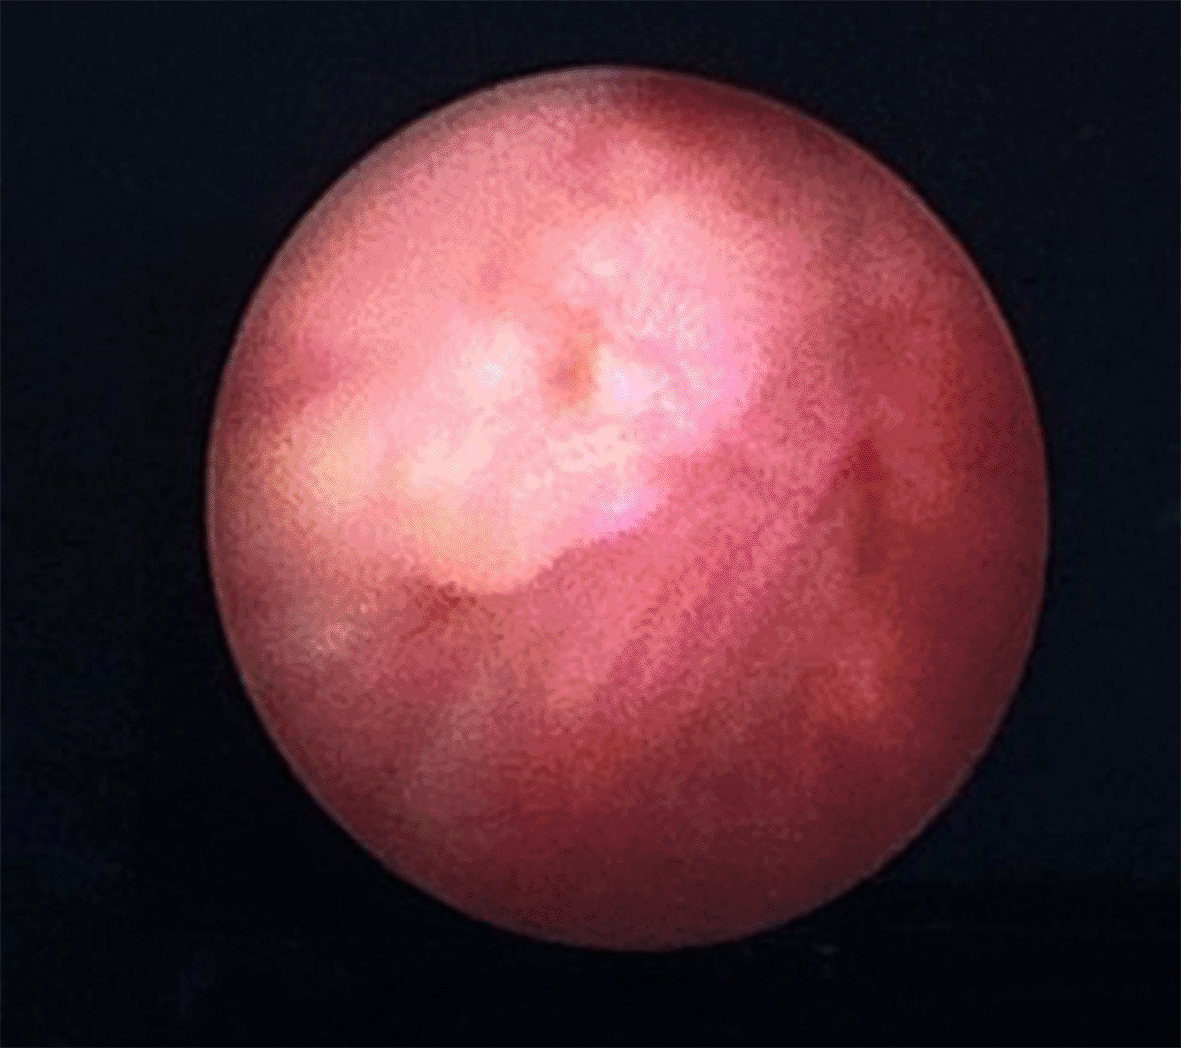

The patient was scheduled for a cystoscopy and urethral mass excision two days later. Cystoscope was inserted through the cystostomy access, showing a tumor infiltration to the anterior wall of the bladder approximately 2 cm from the bladder neck ( Figure 2). Radical urethrectomy and partial cystectomy were then performed through a transurethral approach with antegrade cystoscopy guidance. The excision was extended to the bladder neck and a portion of the anterior segment of the bladder wall which infiltrated by the tumor. We decided to do the bladder preservation and bladder neck reconstruction using remaining anterior bladder wall with the intention to facilitate voiding through the orthotopic site with a Foley catheter, thereby avoiding the need for a permanent suprapubic diversion. The base of the bladder was pulled through the former urethral orifice and sutured ( Figure 3). The surgery was performed without complications and the patient was discharged home within 5 days using silicone foley catheter. The pathology report revealed a urethral adenocarcinoma with clear surgical margins. Neither radiation nor chemotherapy were administered. At the 1-year follow-up, the patient reported satisfaction with her quality of life. The CT scan evaluation showed no signs of recurrence or metastasis.